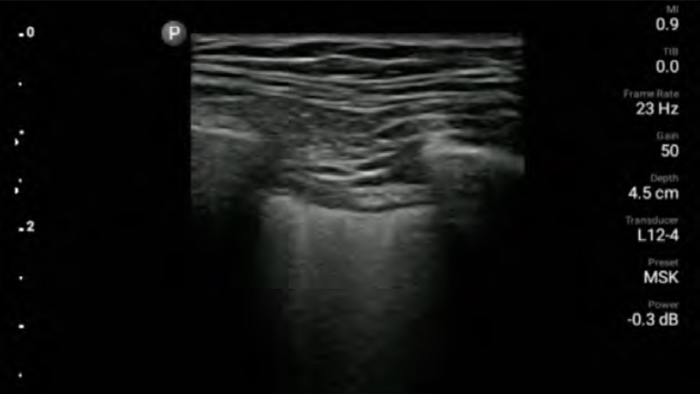

El ultrasonido portátil Lumify para anestesiología le ayuda a visualizar claramente la definición de los bordes con la colocación de la aguja, los nervios circundantes, los vasos sanguíneos y los planos fasciales.

Reduzca las complicaciones en procedimientos guiados por aguja